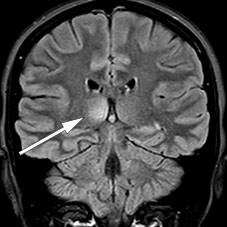

MRI of the brain and total medulla showed enhancement in more than 50 % of the medulla diameter with weak contrast enhancement at levels C4–C5, C6–C7 and Th11–Th12 (Figure 1), but improvement in the lesions that had previously suggested meningitis. The radiologist considered the images to be most consistent with acute disseminated encephalomyelitis. A new lumbar puncture (Table 1) showed an increasing cell count and moderately increased total protein and albumin consistent with blood-brain barrier failure. On the basis of the increasing cell count in the cerebrospinal fluid, aciclovir was again administered until the PCR result for herpes simplex virus came back negative.

Figure 1 Sagittal T2-weighted MRI showed lesions consistent with myelitis at multiple levels.